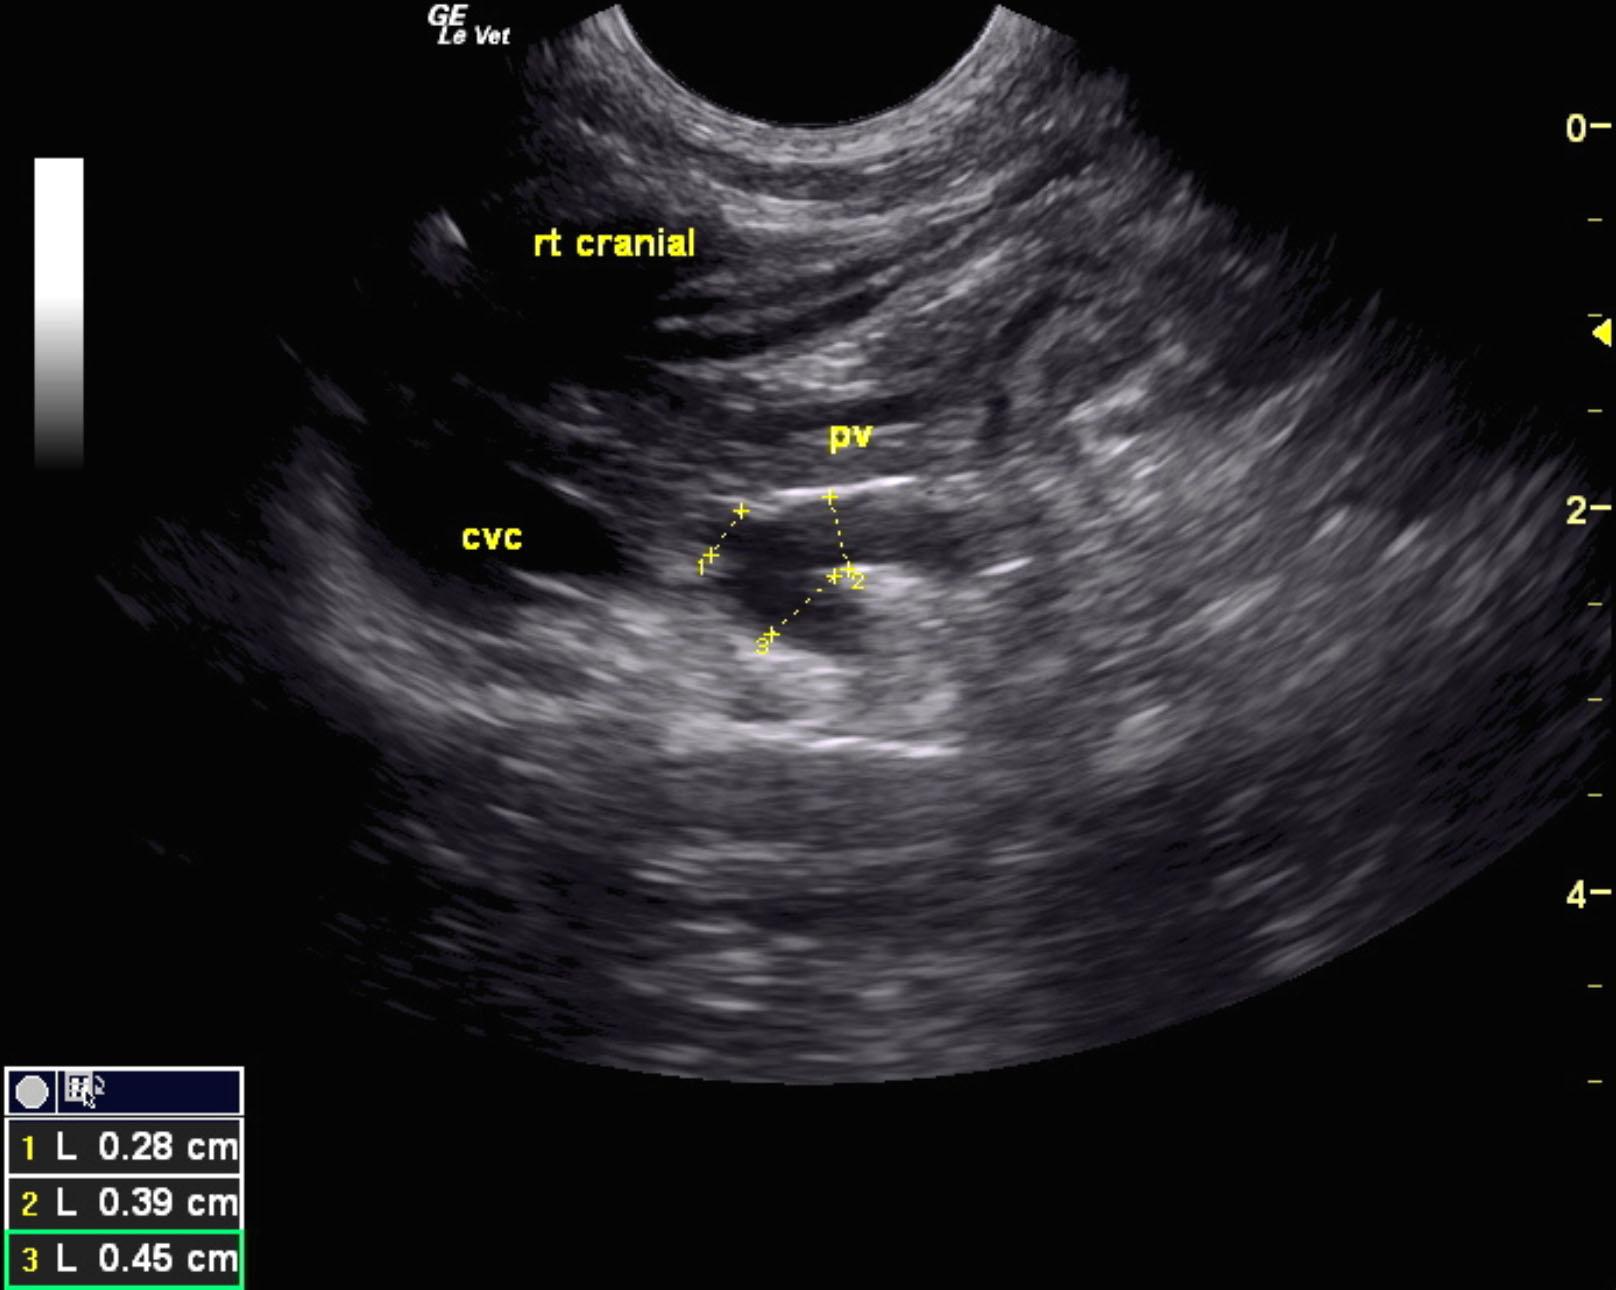

Extrahepatic portosystemic shunt was noted in this patient and measured 0.45 cm in width. The portal vein prior to the shunt measured 0.39 cm and post shunt measured 0.28 cm. This is most consistent with splenocaval shunt. The vena cava prior to the shunt entry measured 0.6 cm and the aorta measured 0.64 cm. The extrahepatic shunt passed dorsally and measured from 0.6 to 1.0 cm in width and entered into the vena cava dorsal ventrally prior to the diaphragm. The vena cava measured 1.0 cm at that point. The liver was subnormal in size and mildly coarse in architecture. The gallbladder was unremarkable.